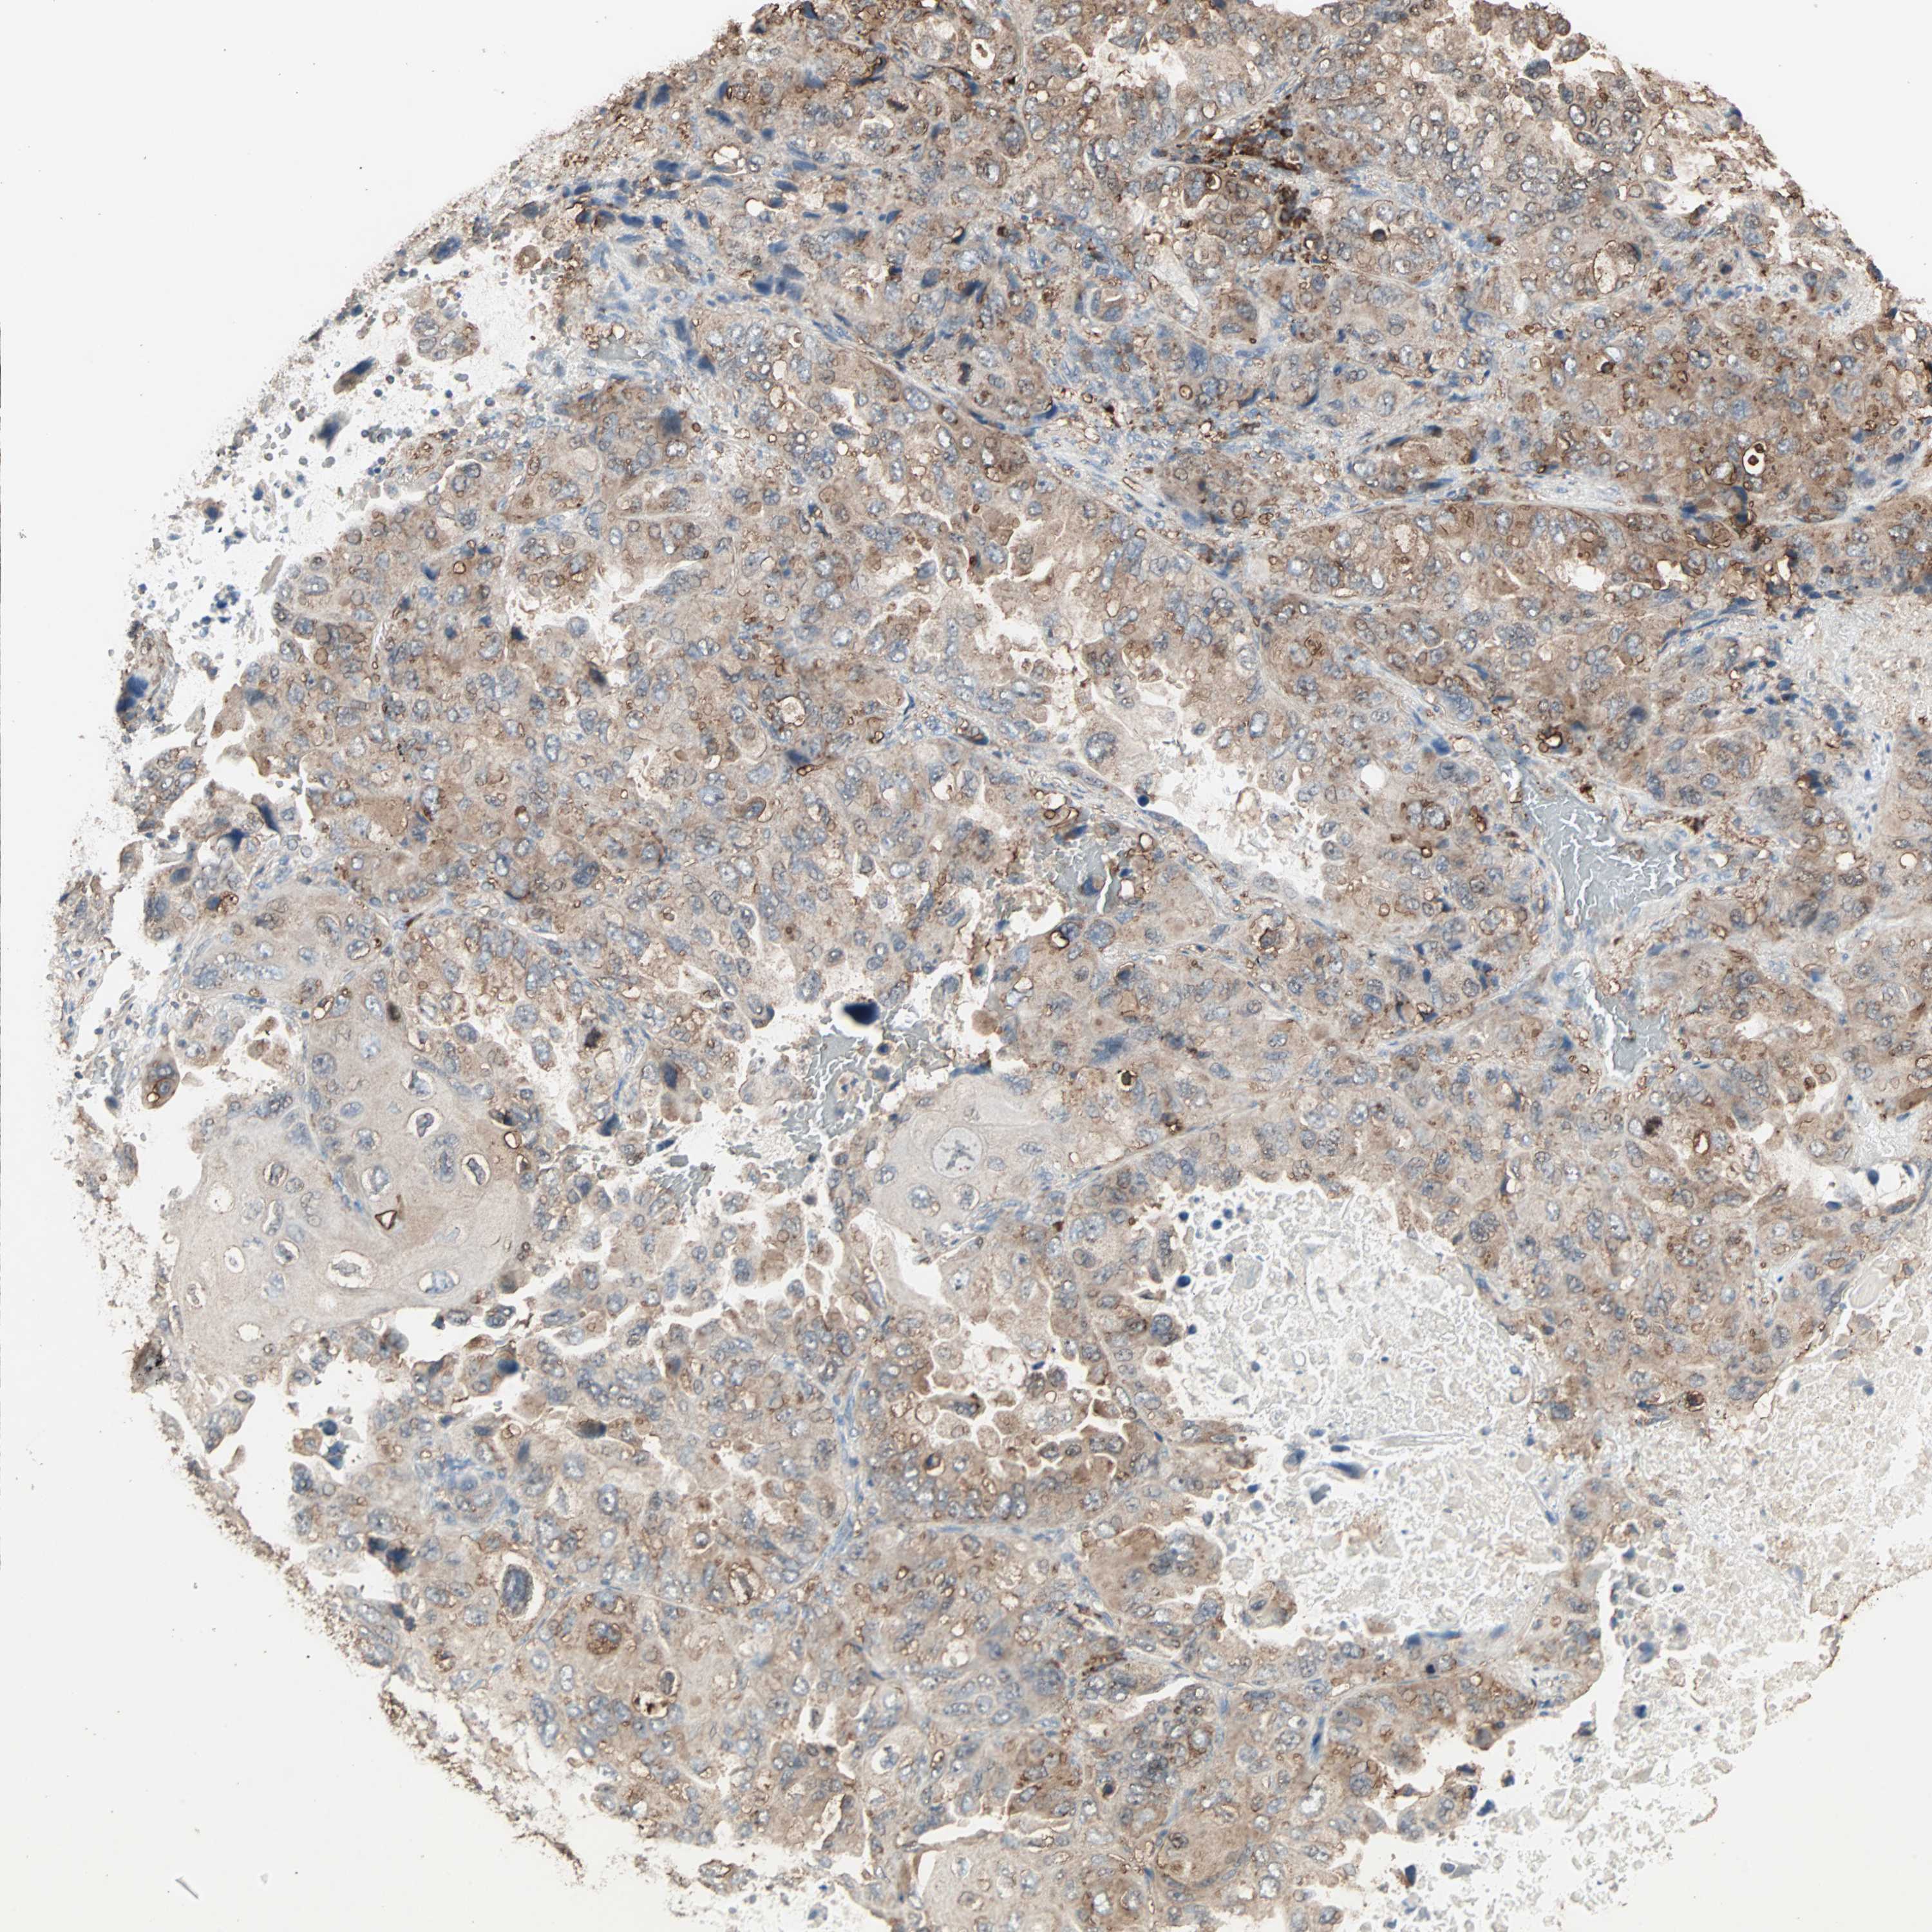

LUNG SQUAMOUS CELL CARCINOMA (TCGA) - Interactive survival scatter ploti

MMP3 is not prognostic in Lung Squamous Cell Carcinoma (TCGA)

: 14.03

Average pTPM 13.2

Number of samples 489